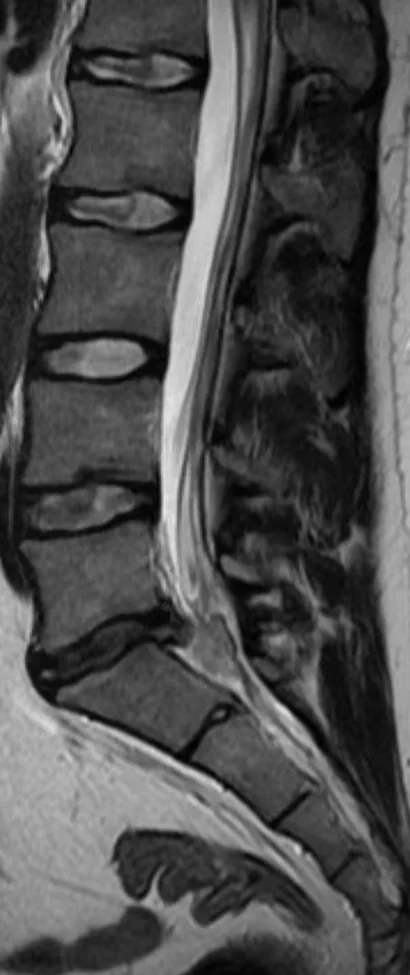

Vaivaksi jäi puutunut ja heikko jalka. Reisi hieman puutunut, pohje ja jalan ulkosyrjä sekä ulommat varpaat puutuneimmat. Kävin itse MRIssä kun ei lähetettä saanut. Pullistuma painaa (L5) S1 juuren tyvialuetta.